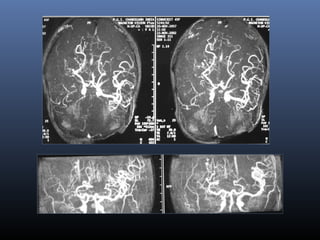

Moya- Moya disease- Imaging

Pial synangiosis- Dilated superficial

temporal and middle meningeal arteries

 Infarctions-

 Intense enhancementof basal ganglia

 Enhancement of dilated deep medullary veins in

centrum semiovale

 Pial collateral enhancement

 DSA- Puff of smoke appearance

Post pial synangiosis